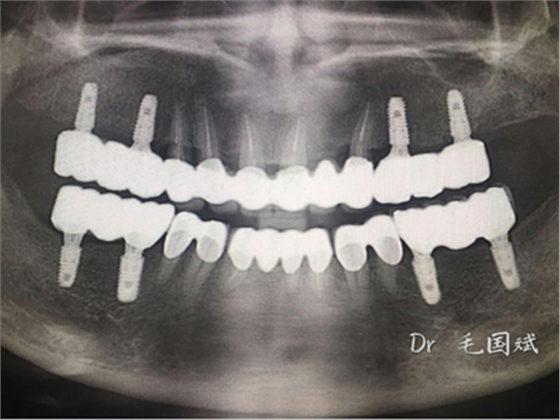

毛國斌種植病例——群討論分享